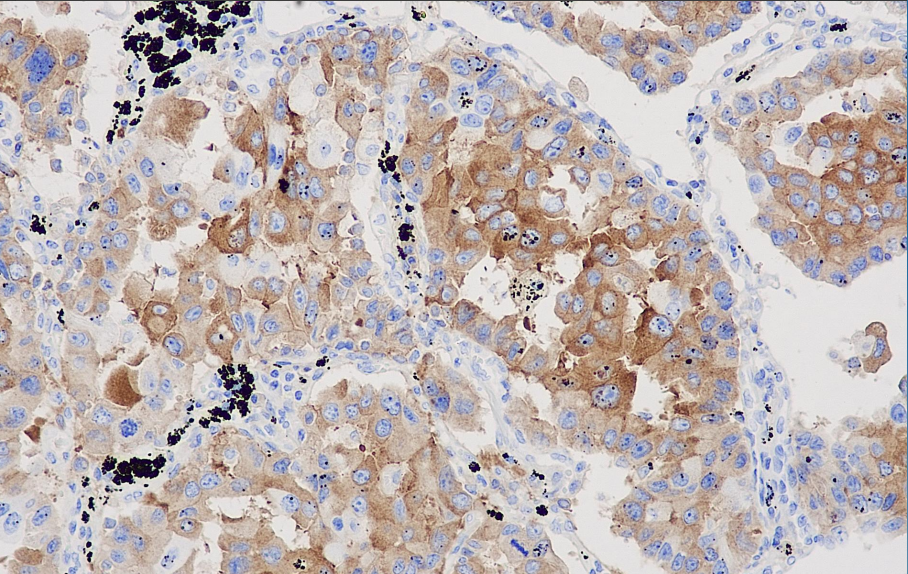

Cellular localization: cytoplasm/membrane

Positive control: Lung adenocarcinoma

The human polydrug resistance gene family contains at least six similar genes, which encode MRP-1, MRP-2, MRP-4, MRP-5 and MRP-6. Among them, MRP-3 is a complete membrane protein with a size of 190 to 200kDa, mainly used in the research of tumor drug resistance mediated by non-P-glycoprotein MRD.

The MRP3 antibody reagent can specifically bind to the MRP3 molecular antigen. The immunohistochemical kit containing the MRP3 antibody reagent is suitable for the assessment of multidrug resistance in tumors.